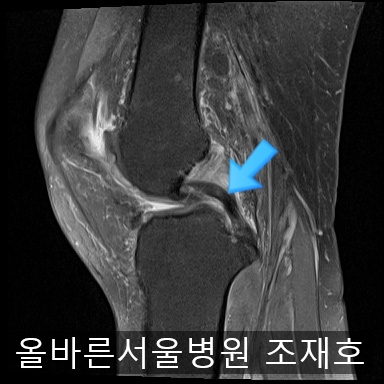

为了掌握具体情况拍了MRI。

髌骨关节虽有炎症,但仍保留相当一部分软骨。

内侧关节软骨几乎不见,软骨板也受损严重。软骨损伤部位充满关节液。

后方十字韧带无明显异常。